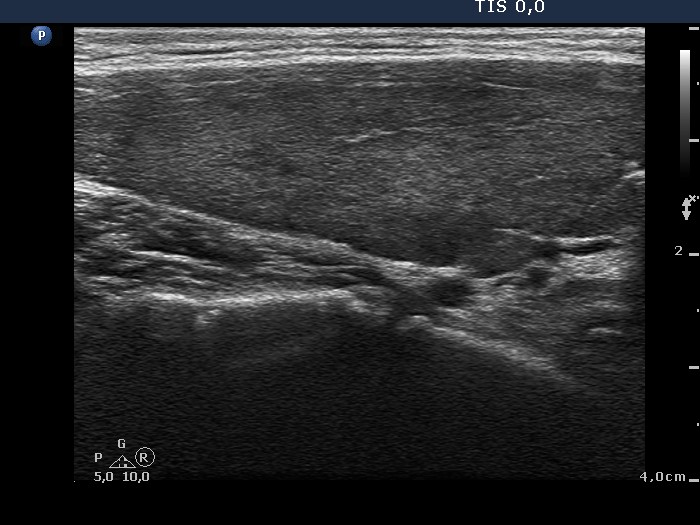

Graves' disease - Case 14. (ultrasonographic picture 2)

Right lobe, longitudinal scan.